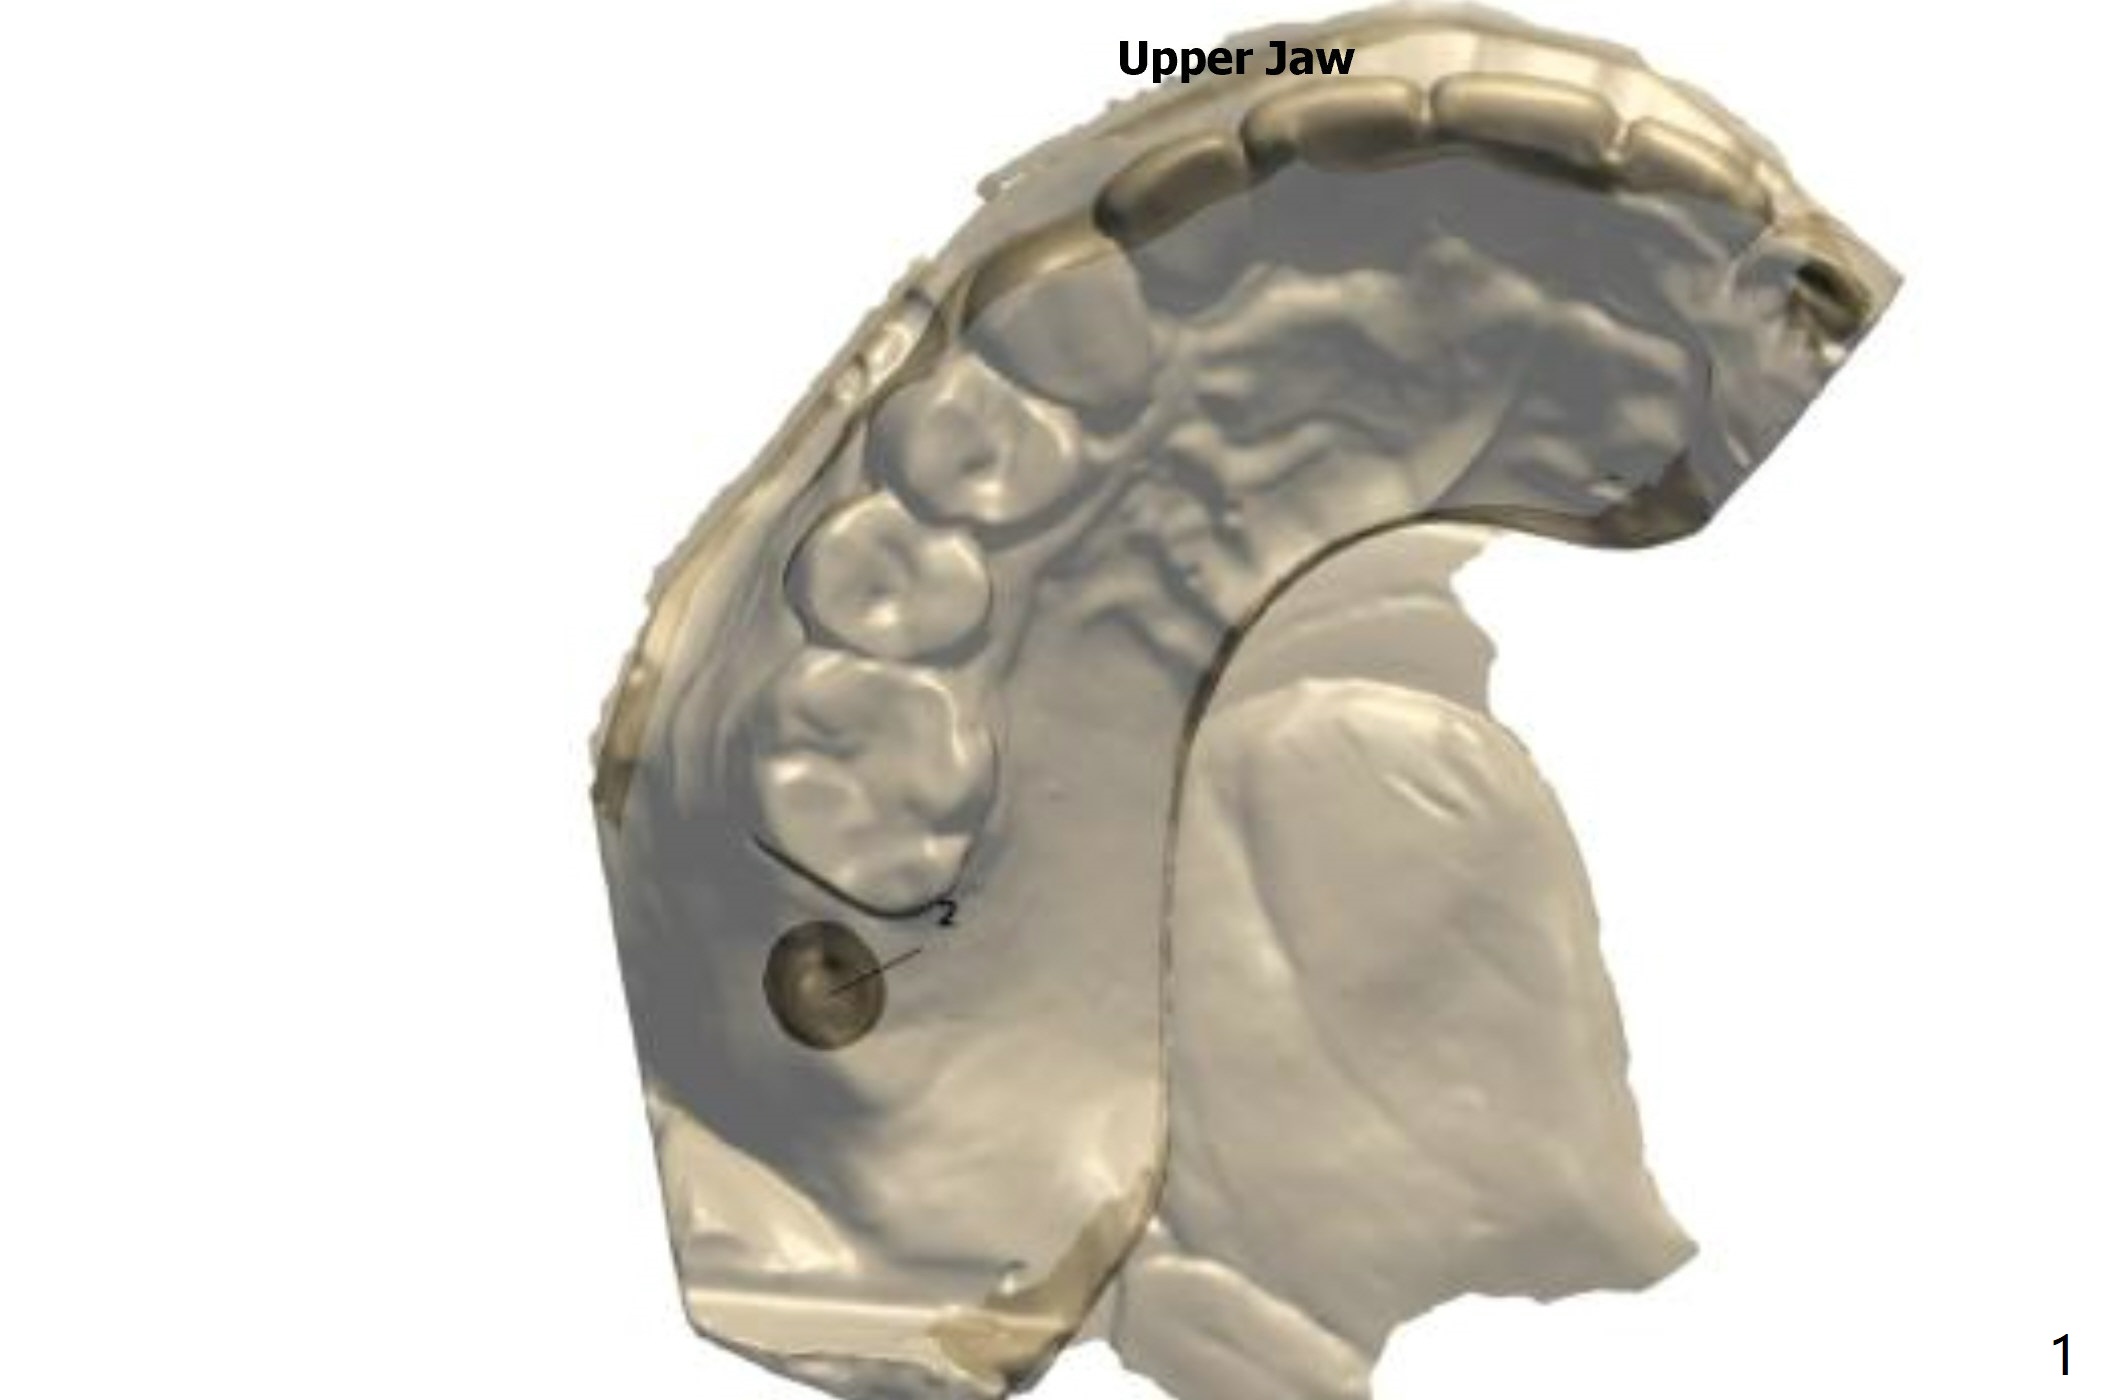

No Sinus Floor No Sinus Lift

Four months post #2 implant removal (without sinus floor) and bone graft, a 5x8.5 mm implant will be placed without sinus lift.

Upper Molar

Immediate Implant,

Trajectory